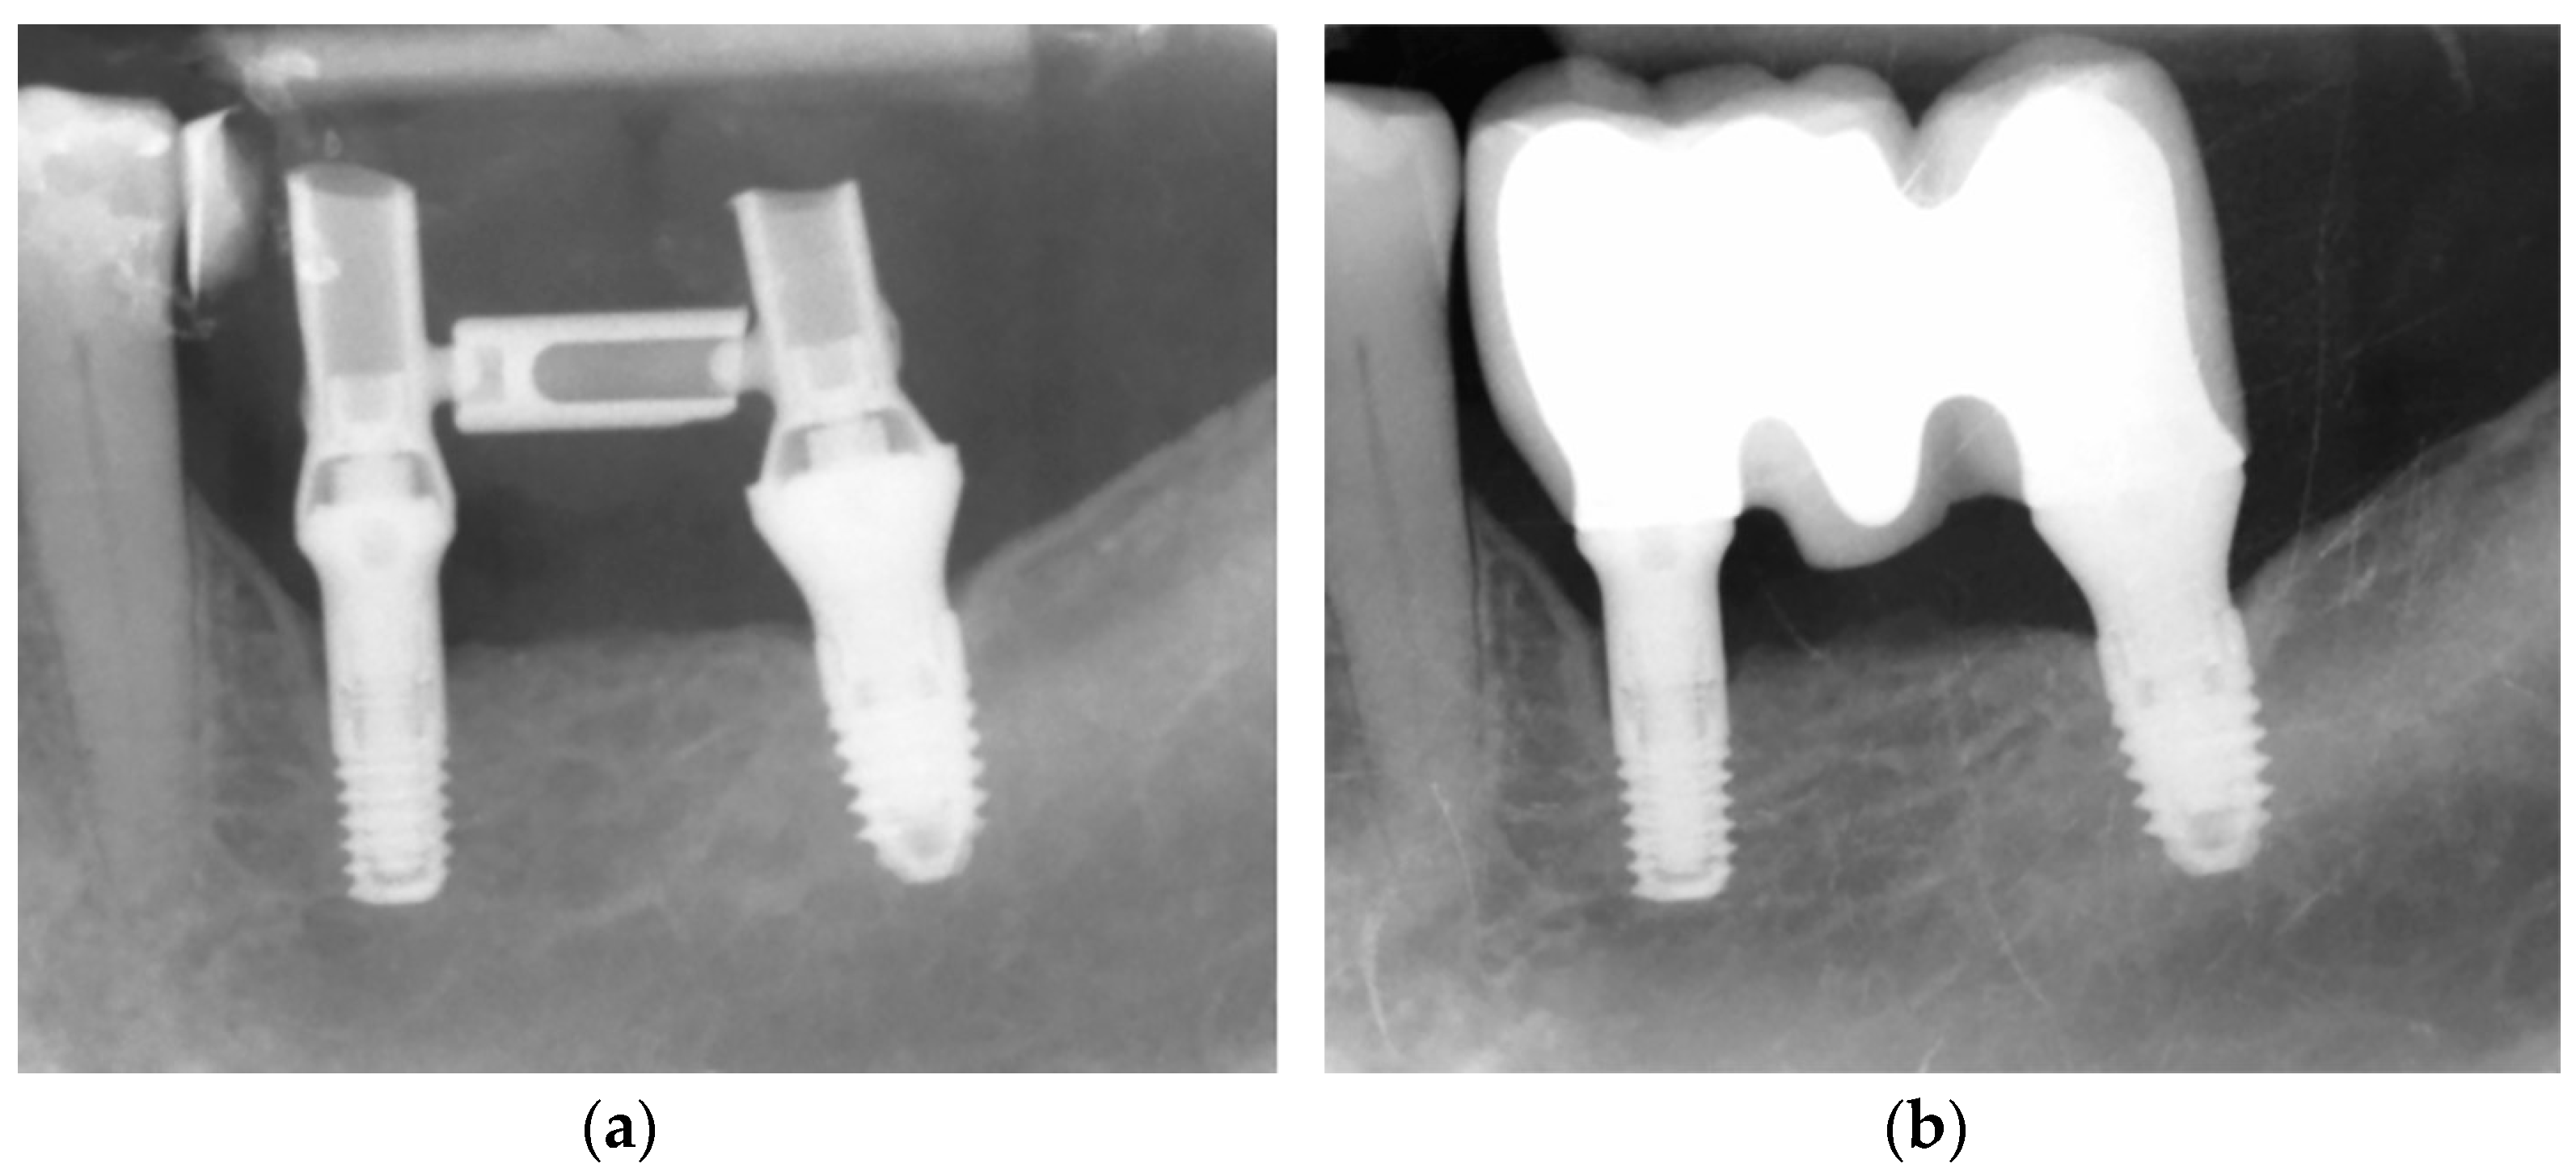

2.5. Interventions

The Following Visit Schedule Was Employed for All the Participants